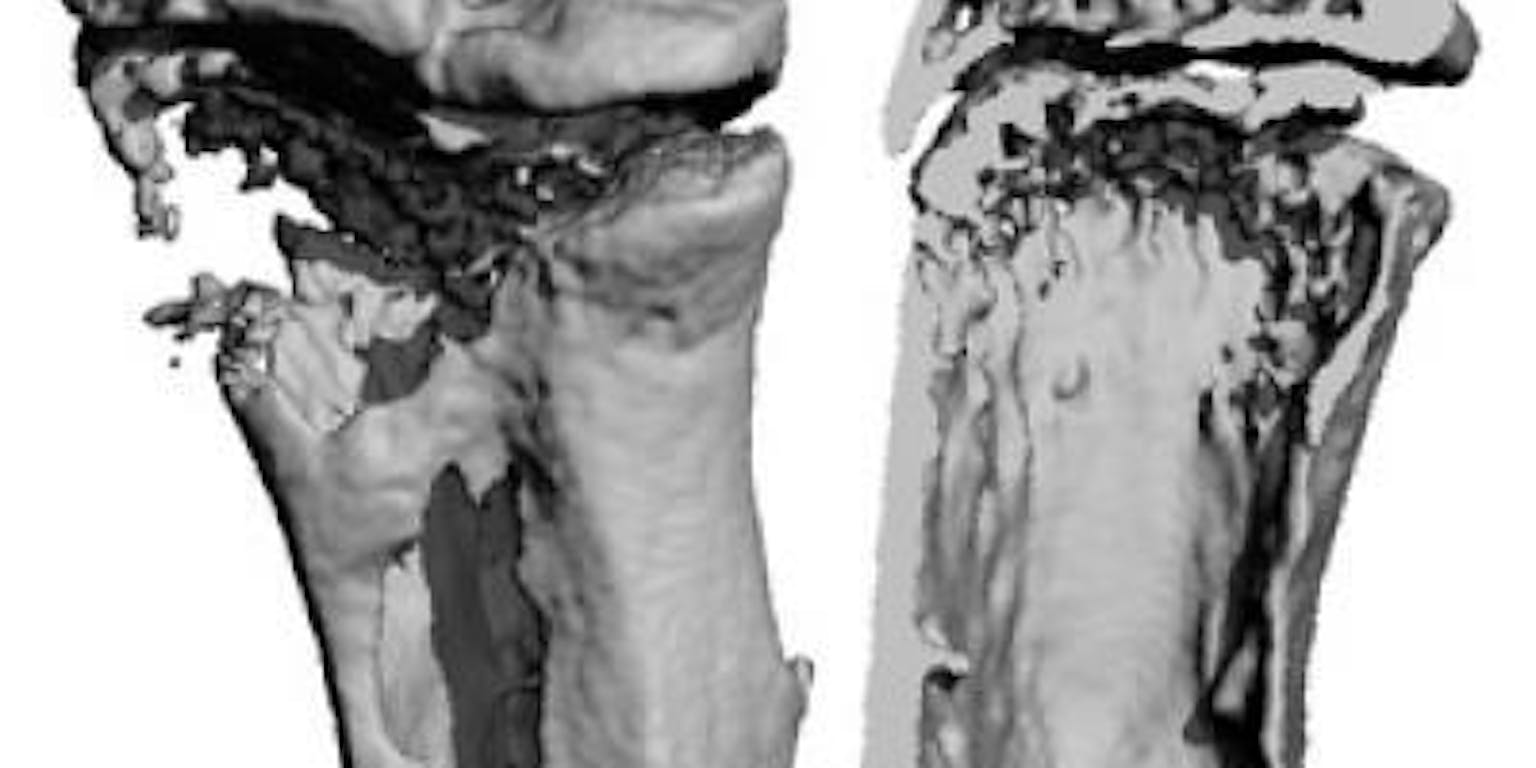

Soms is een botbreuk zo ernstig dat het beschadigde moet worden vervangen door een botimplantaat. Het gebeurt ook dat tumoren gaten achterlaten in het bot die te groot zijn om vanzelf dicht te groeien. De onderzoeksgroep van Clemens van Blitterswijk werkt al ruim twintig jaar aan de verbetering van botimplantaten.

Hij probeert het materiaal slimmer te maken. In de regeneratieve geneeskunde wil dat zeggen: een materiaal dat niet alleen beschadigd bot vervangt, maar ook de aanmaak van nieuw botweefsel stimuleert. Van Blitterswijk en zijn team ontwikkelden nieuwe botvullers die het zelfherstellend vermogen van de mens aanspreken. Deze nieuwe generatie biomaterialen levert hem de Huibregtenprijs voor wetenschappelijk vernieuwend onderzoek op.